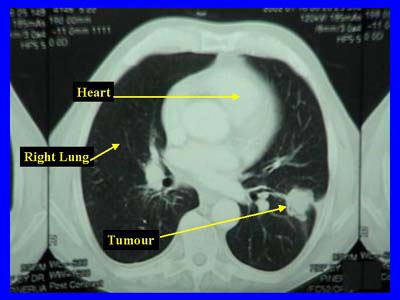

Den Grund dafür gibt Dr. Rudolf Kaaks vom Deutschen Krebsforschungszentrum in Heidelberg damit an, das Frauen häufiger an einem Adenokarzinom der Lunge erkrankten als die männlichen Probanden und diese Tumorart leichter im CT nachweisbar sei, da sie häufig im peripheren Lungengewebe auftritt. Andere Arten von Lungenkrebs entstünden dagegen häufig zentral an den Bronchien, wo sie auch im CT erst auffallen, wenn sie größer sind.